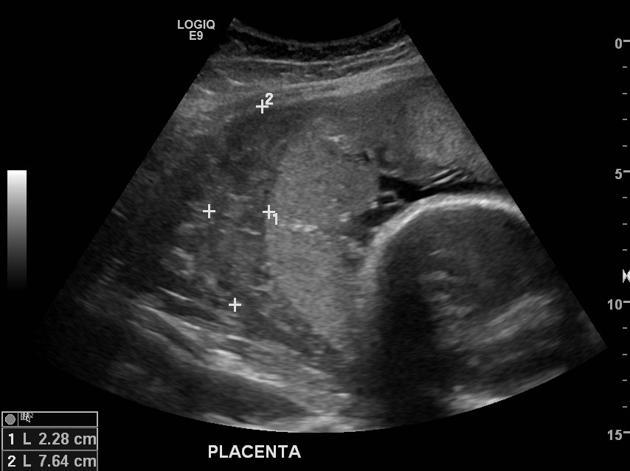

● Retroplacental hematoma patterns

● Case-based interpretation